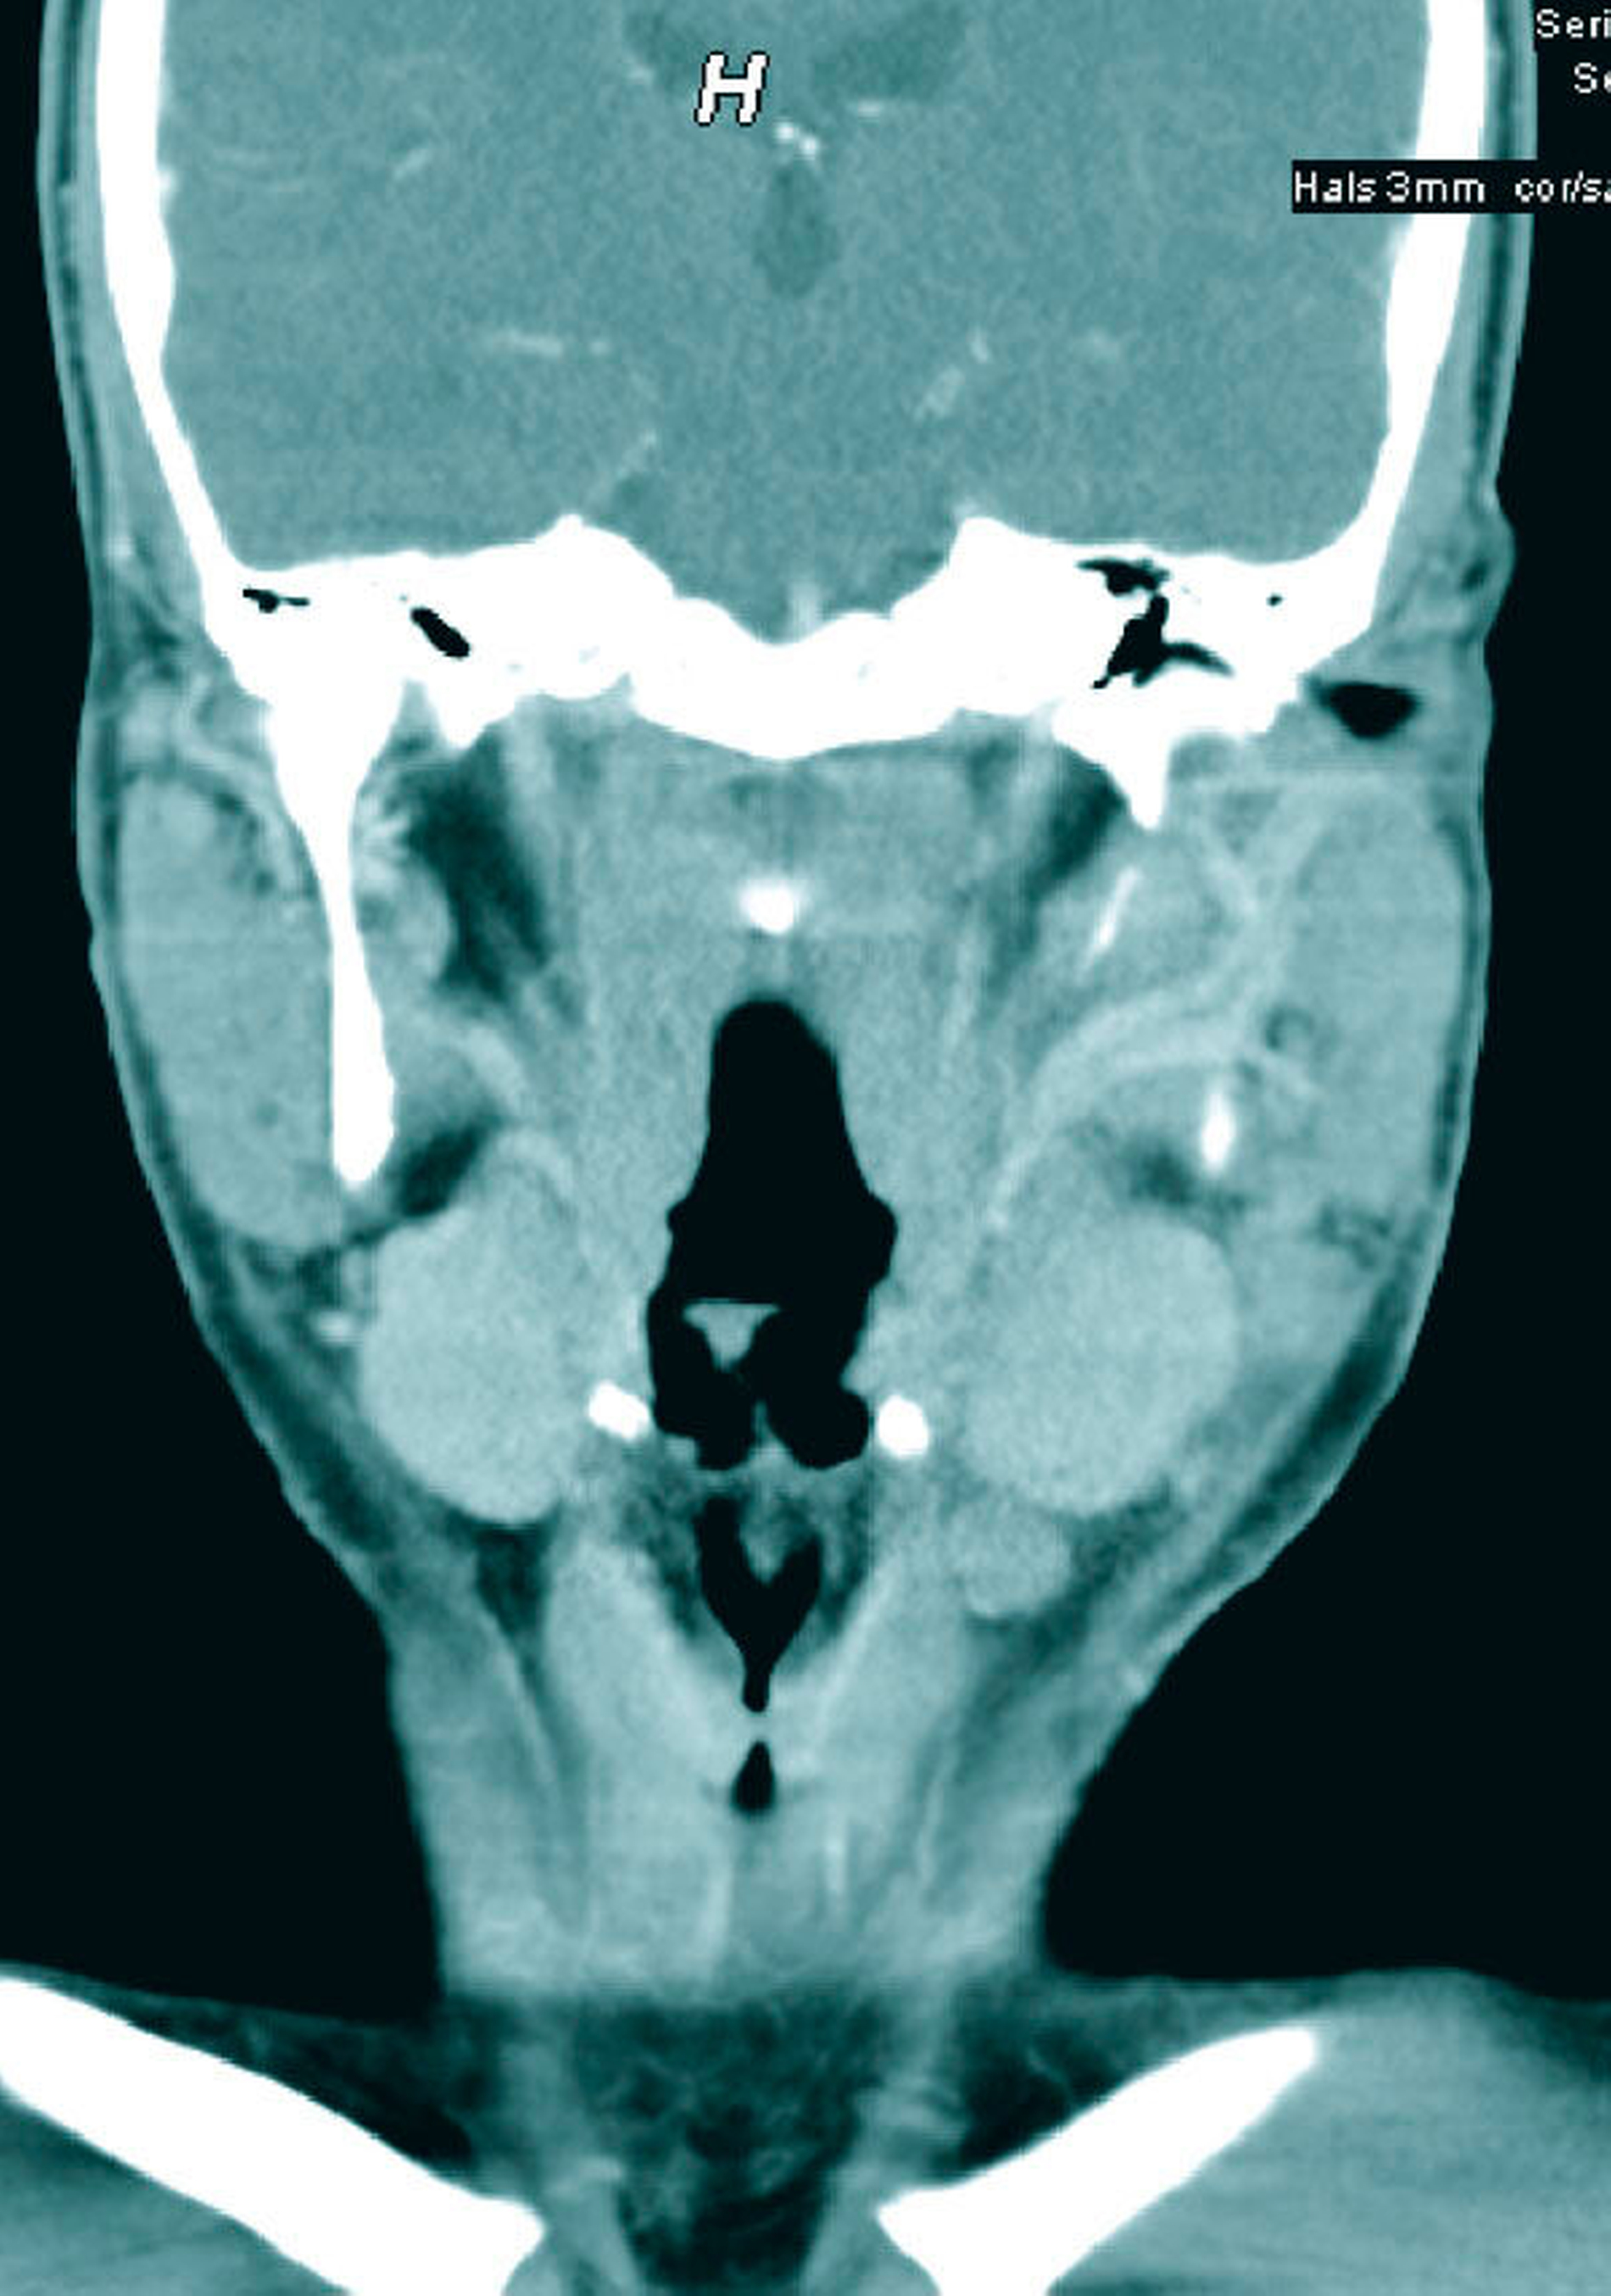

Die serologische Blutuntersuchung ergab eine starke Erhöhung der C-reaktiven Proteine und der Leukozyten. Im Ultraschall und in der Kontrastmittel-verstärkten Computertomografie (CT) ließ sich eine Vergrößerung der zervikalen Lymphknoten darstellen (Abbildungen 1 und 2). Weitere Befunde oder Foci ließen sich nicht nachweisen.

Die klinische Diagnostik ist bei der Lymphknotentuberkulose von enormer Bedeutung, da sie bei Bestehen einer B-Symptomatik (Nachtschweiß, Müdigkeit, Gewichtsverlust) nicht selten mit akuten Infekten wie etwa der Influenza verwechselt wird. Die Ausprägung der Symptomatik ist allerdings patientenabhängig, sodass die Infektion aufgrund eines möglichen atypischen Verlaufs unerkannt bleiben und sogar letal enden kann [Kalaidina et Holbrook, 2018]. Bildgebende Verfahren wie Ultraschall, CT, MRT oder minimal-invasive Eingriffe wie die Feinnadelaspiration – die aber wegen der Verschleppung von Zellen kontrovers diskutiert wird – können aufschlussreich sein. Mikrobiologische und molekulare evaluierte Verfahren sind Nukleinsäure-amplizierende Tests (zum Beispiel PCR), Interferon-Gamma-Release-Assays (zum Beispiel der Quantiferon-Test, TB-Spot-Test), Kulturanlegung und mikroskopische Untersuchungen von Exzisionsbiopsien. Die mikrobiologische Diagnostik mit Kultivierung der Bakterien ist die Methode der Wahl (Goldstandard), da sie zum einen die Bestimmung der mykobakteriellen Spezies und zum anderen die Untersuchung auf medikamentöse Unverträglichkeiten und Resistenzen erlaubt [Schaberg et al., 2017].